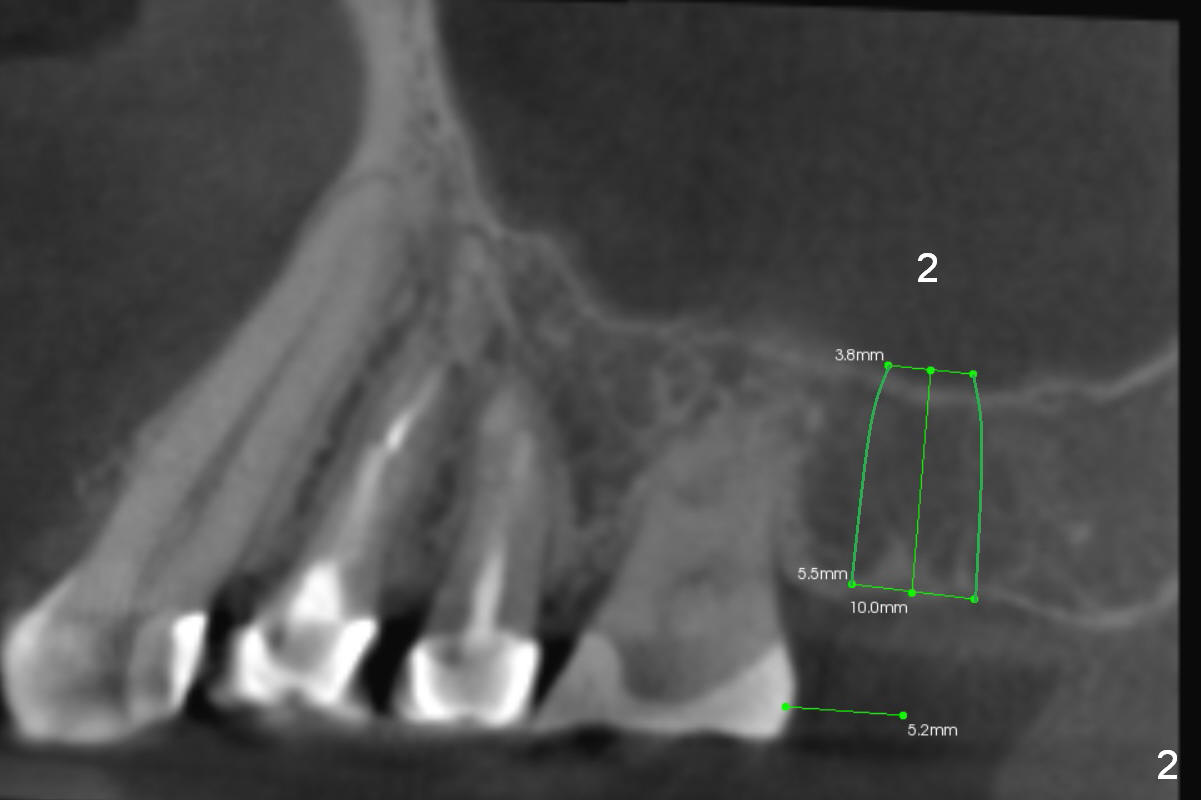

A 60-year-old woman has lost the tooth #2 for a few years (Fig.1). Since then, three of her anterior teeth have fractured and required implant placement (#8, 10,11). It appears that restoration of the tooth #2 may alleviate further anterior breakdown. There are 2 challenges associated with this case: supraeruption of the opposing teeth and low bone density (40-200).

To tackle the 1st challenge, place an implant as deep as possible and reduce the opposing tooth as early as possible (immediately after implant placement with immediate provisional if possible).

To handle the 2nd challenge, start bone expansion with #15 and osteotomes (from 8 to 11 mm). Set implant spacer at 4 mm (Fig.2). Prepare allograft (.5-1 mm) and Osteogen (4:1 ratio) for sinus lift. Place 8 mm stopper on the larger condenser from Sinus Master Kit.